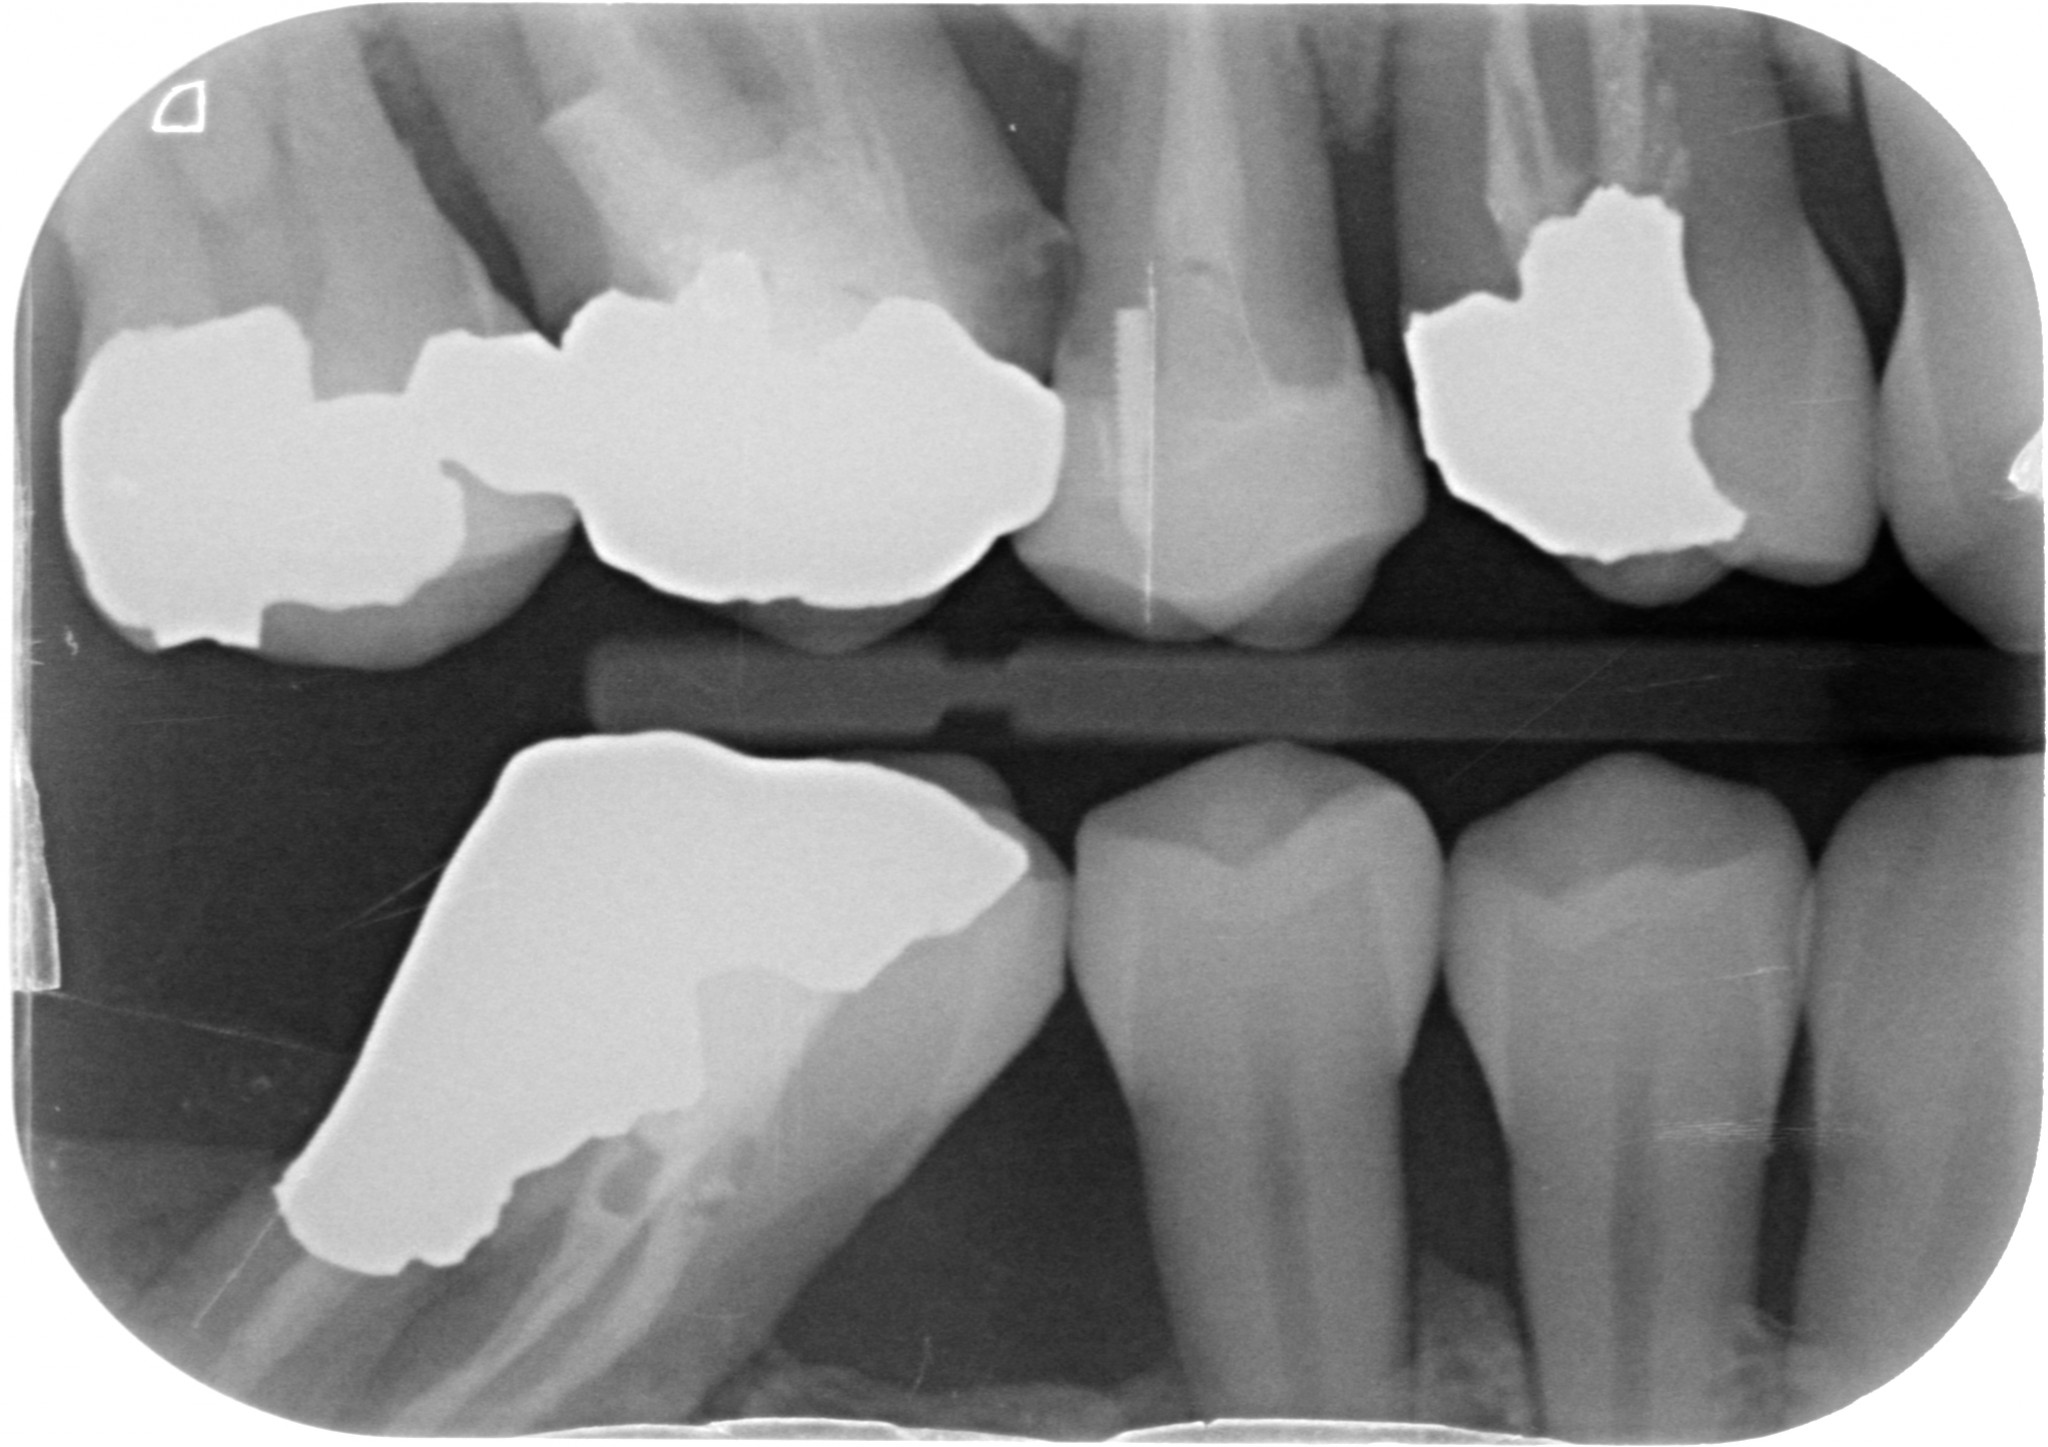

La tecnica prevede di montare una automatrix di quelle basse (la più piccola) e di inserire, all’interno della sua circonferenza, dal lato interessato dalla lesione, una matrice sezionale che abbia una bella pancia allungata e sufficientemente larga da comprendere in senso orizzontale la cavità (in certi casi ne monto addirittura due una di fianco all’altra per riuscire a girare anche in senso vestibolare o linguale/palatino). Di solito per questo uso le matrici Palodent V3 più alte, quelle che vedi in questa foto.

L’automatrix fa da ottimo appoggio per tenere ferma la matrice sezionale, che può essere portata in posizione utilizzando uno specillo, una Heidemann o una spatola piatta da composito. Una volta che siamo riusciti a guidare la matrice tra gengiva e gradino cervicale, tenendola premuta con un dito, stringiamo l’automatrix con l’altra mano.

La maggior parte delle volte riusciamo ad ottenere un perfetto adattamento al gradino cervicale.

In certi casi si può aggiungere un cuneo, a volte per tenere bene accollate le matrici alle zone che ci interessano spingendolo sottogengiva, in altri casi lo si posiziona più coronalmente solo per stabilizzare l’automatrix.